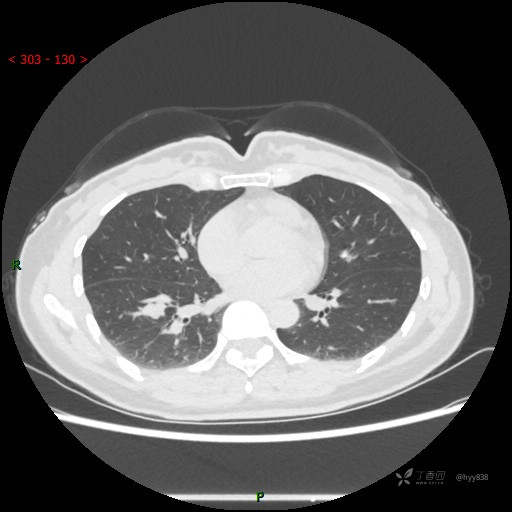

简要病史:患者2年前体检行胸部CT提示:右肺结节,当时结节较小,建议其定期复查,患者未在意。近期患者自觉呼气不畅,无畏寒发热,无咳嗽咳痰,无心慌胸闷胸痛,无头晕头痛,无腹痛腹泻,无四肢肌肉酸痛等不适,于当地医院行胸部CT提示:右肺下叶结节灶(18*10mm),现为求进一步诊治来我院就诊,门诊以“肺结节”收入我科。 自起病以来,患者精神、饮食、睡眠可,大小便正常,体力、体重未见明显异常。

辅助检查:CT

增强动脉期